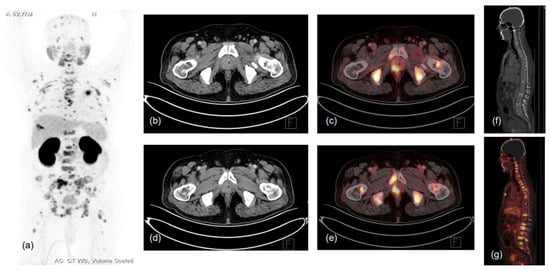

5. Biochemical Recurrence and Metastatic PCa

7. Treatment Response Evaluation and Modulation of PSMA Expression by ADT